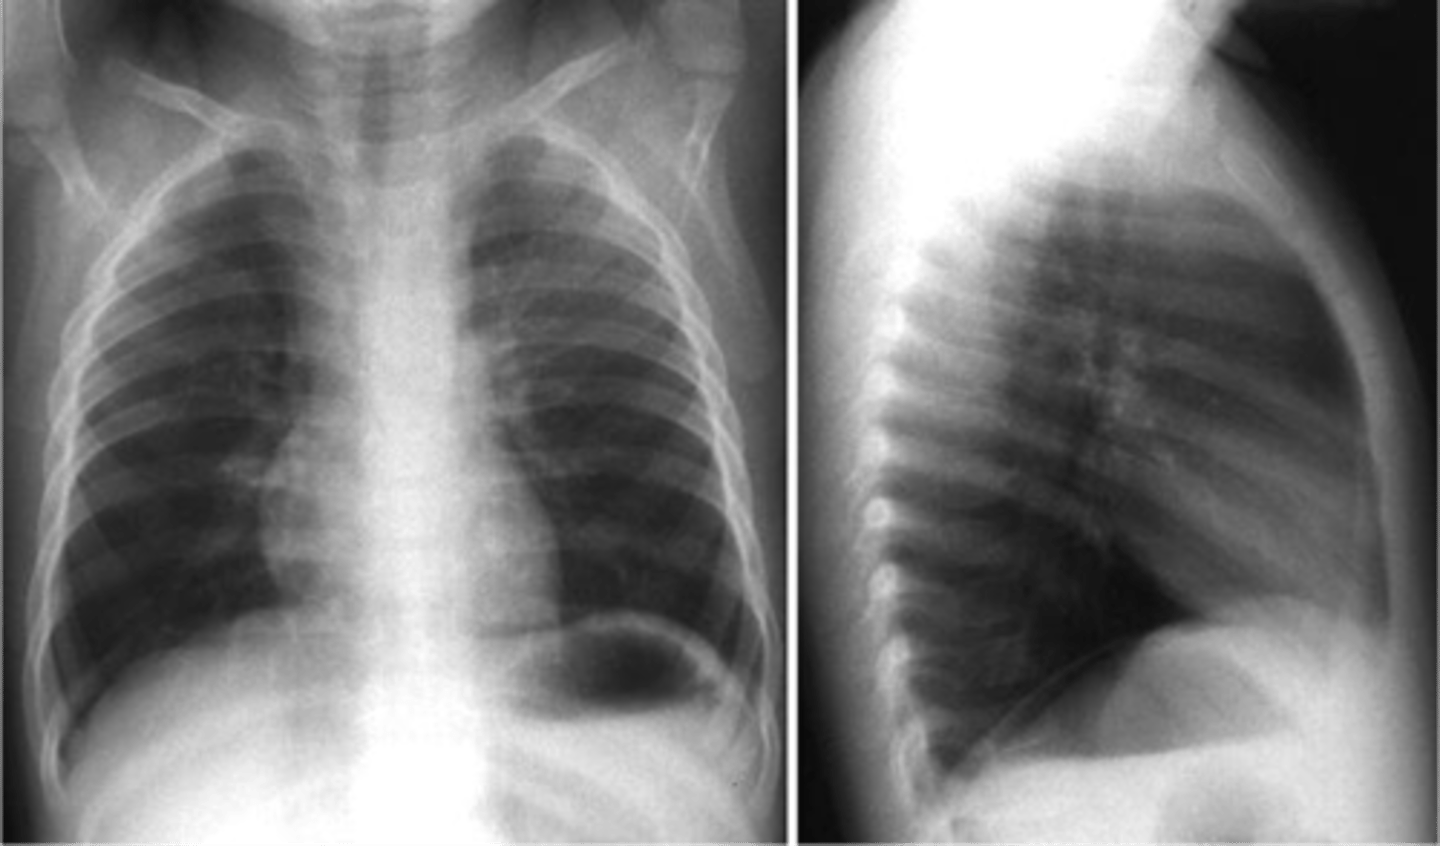

Epiglottitis (thumb sign)

steeple sign (croup)

steeple sign (croup)

Croup

Steeple sign- group